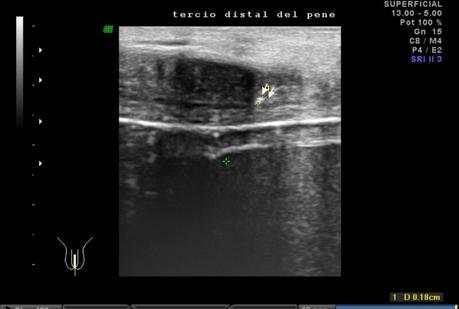

A nivel de base del pené, entre los cuerpos cavernoso y esponjoso en su porción central se observa la presencia de calcificación, que mide 2.2 mm. En tercio distal del pené, a nivel de cuerpos cavernosos con presencia de calcificación que mide 1.8 mm.

A NIVEL DE BASE Y TERCIO DISTAL DEL PENÉ, EN CUERPOS CAVERNOSOS CON PLACAS A RELACIÓN A ENFERMEDAD PEYRONIE.